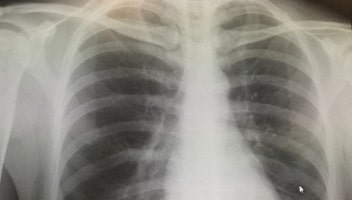

肺小細胞癌の検査

小細胞癌は、胸部エックス線で中枢側の腫瘤性陰影、肺門や縦隔のリンパ節の腫大が確認できることがあります。